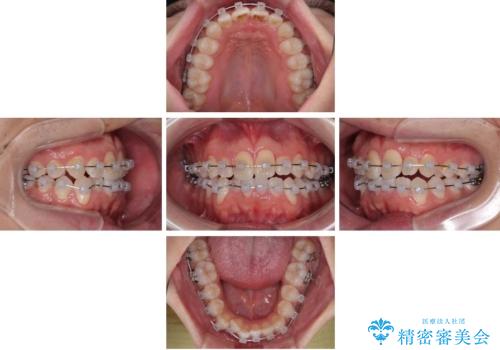

- クリアブラケット

- 1年2ヶ月

- 「上下の前歯がガタガタしているのが気になる」とのことで来院された患者様です。

上下顎前歯部に叢生(歯の重なり・ガタつき)を認め、見た目だけでなく、歯磨きのしにくさも気にされて来院されました。

そのため今回は、プラスチックブラケット+メタルワイヤーによるクリアブラケットによる治療を選択しました。